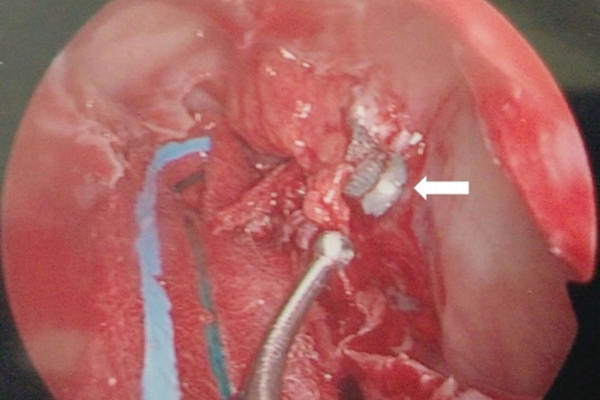

Trans-sinus endoscopic removal of retrobulbar air gun pellet within the orbital apex